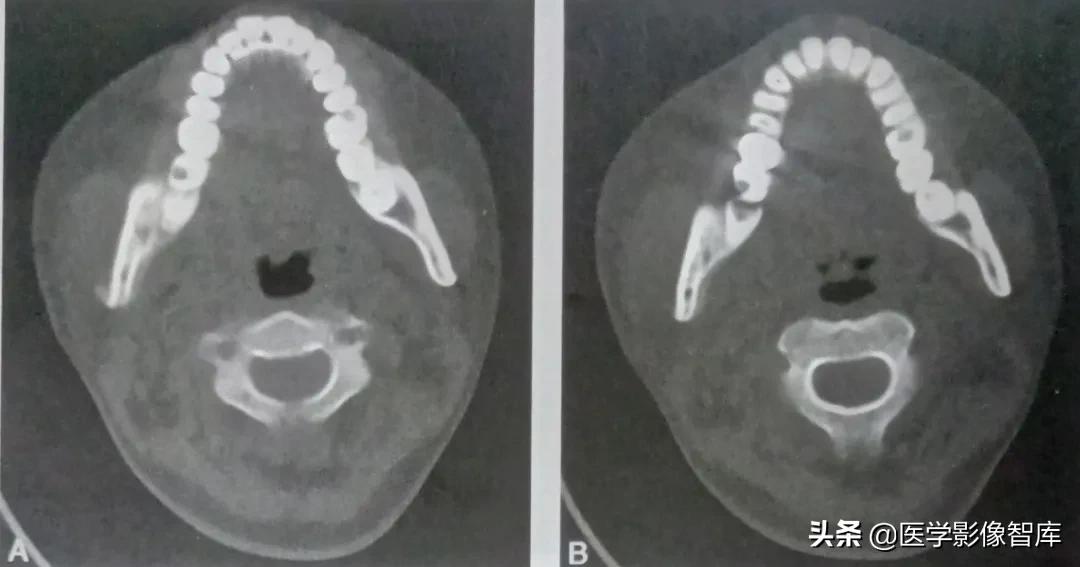

患者,女,28岁。右下颌骨疼痛流脓1个月。诊断为右下颌骨化脓性骨髓炎,见图2

图2 右下颌骨化脓性骨髓炎

轴位连续层面示右下7龋坏,牙根周颌骨破坏,可见不规则层状骨膜反应。